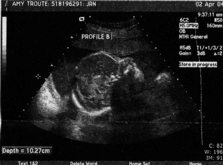

Troute Twins Update!  We had another ultrasound (4-2-04) – this one only lasted an hour and the tech was SO much nicer and better than the last one.  It was actually enjoyable!!

The babies are doing GREAT – measuring at 26 weeks, 1 day and I’m “technically” only 25 weeks 4 days along (hey – every little bit counts, right?).  Baby A is 2lbs 2oz and Baby B is an even 2lbs.  :o)  they’re kind of in “yin and yang” position now – so cool to finally get a visual on how they’re positioned.  Baby A is still the more active of the two – it’s feet are right up at my right rib cage, head down by my bladder and Baby B’s head is just above my belly button and feet are down at my left hip.  :o)  I can’t stop smiling, can you tell!!?

At one point we were able to get face-to-face with Baby B... It was yawning and touching its face cute little lips and nose and chin... I got all teary, Reese grabbed my hand what a moment!! Baby A was facing my back so we didnt get to see its face bummer! Stubborn little thing! Maybe well see its face at next months ultrasound were supposed to have one each month that remains... Yay!